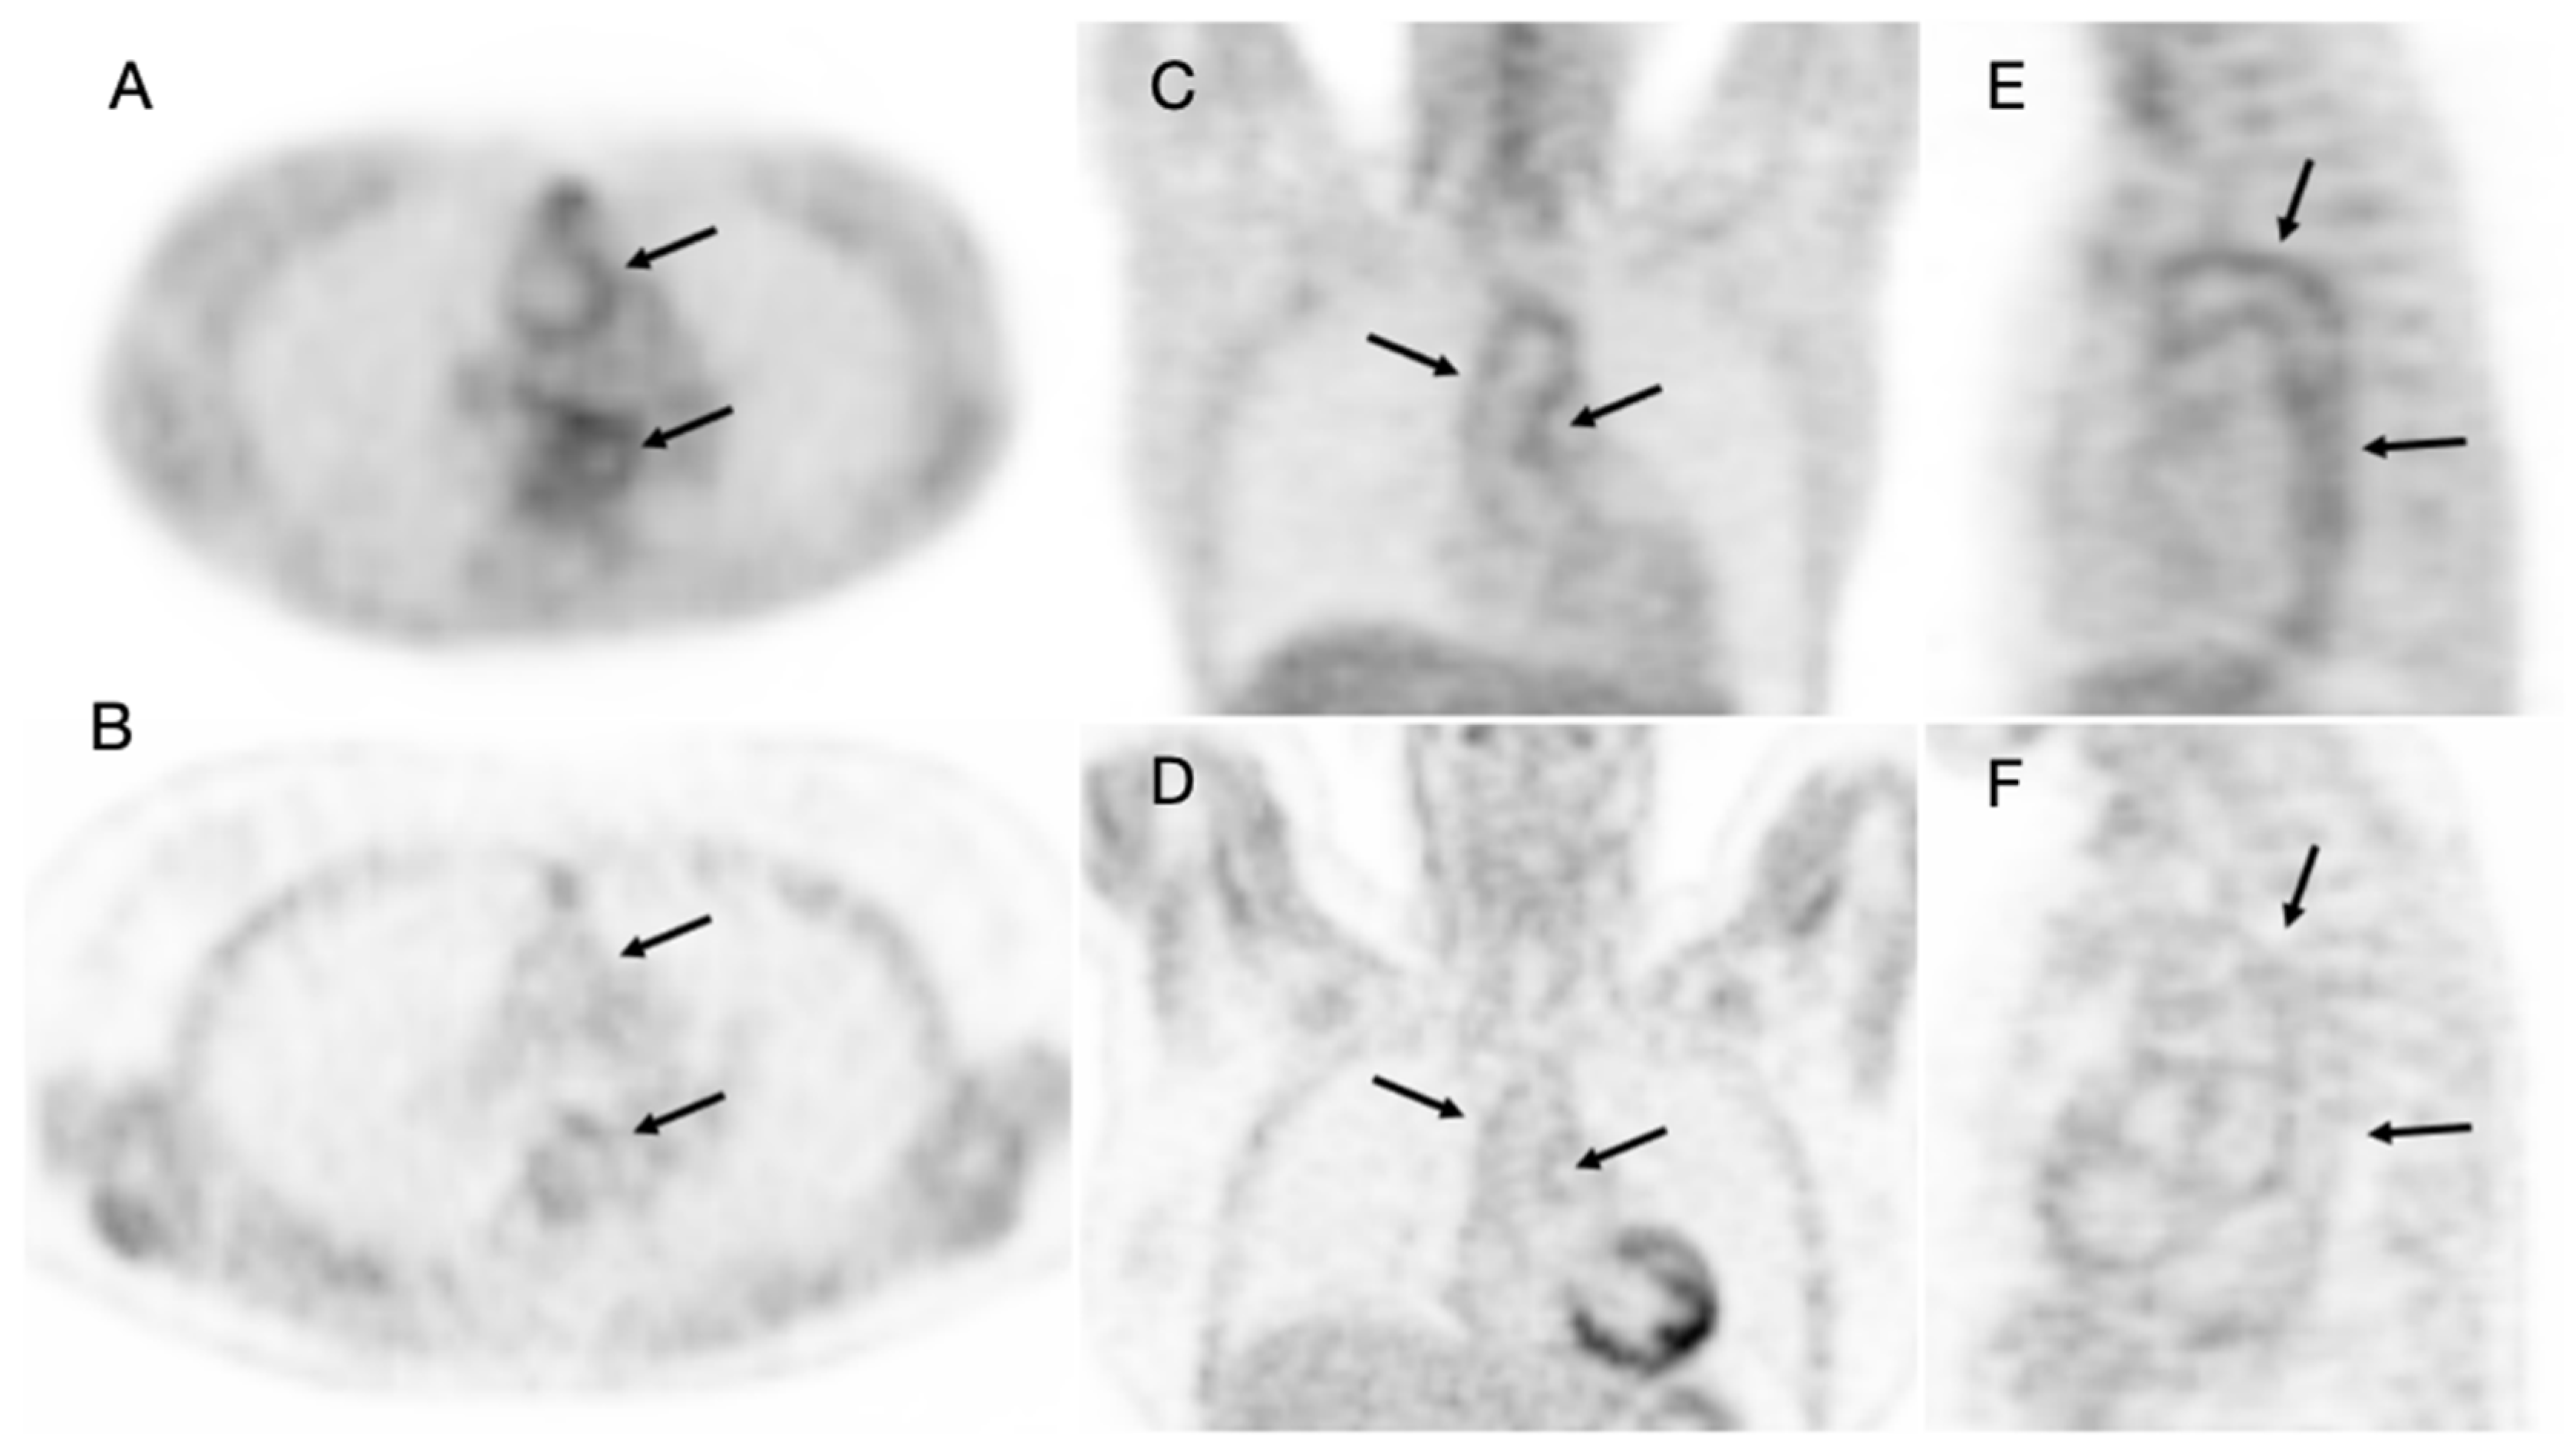

Figure 3 and Figure 4 show two representative cases for both groups of patients at 24 months of follow-up.

Figure 4. An initial PET scan (A) axial, (C) coronal, (E) sagittal slices in a 47-year-old woman with Takayasu arteritis. Images showed FDG uptake along the thoracic aorta (arrows). After 24 months of TCZ therapy, the patient presented a good clinical and biochemical response and the follow-up PET (B) axial, (D) coronal, (F) sagittal slices showed the normalization of FDG uptake at the thoracic aorta wall (arrows).